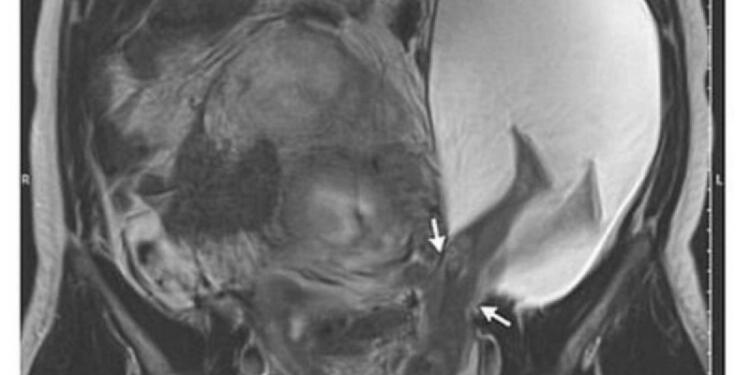

Συγκεκριμένα, μια έγκυος γυναίκα στην Κίνα σώθηκε χάρη στους γιατρούς, αφού το αγέννητο μωρό της κλώτσησε τη μήτρα της σε μια “εξαιρετικά σπάνια” περίπτωση. Η αγέννητη κόρη της κ. Ζανγκ λέγεται ότι κλώτσησε την ίδια τόσο σκληρά, που έσκαψε μια πληγή στον τοίχο της μήτρας της, η οποία είχε μείνει από μια προηγούμενη εγχείρηση.

Το κοριτσάκι γεννήθηκε στις 35 εβδομάδες με καισαρική τομή και η ίδια αλλά και η μητέρα της βρίσκονται σε σταθερή κατάσταση, σύμφωνα με το Νοσοκομείο Shenzhen του Πανεπιστημίου του Πεκίνου στη νότια Κίνα.